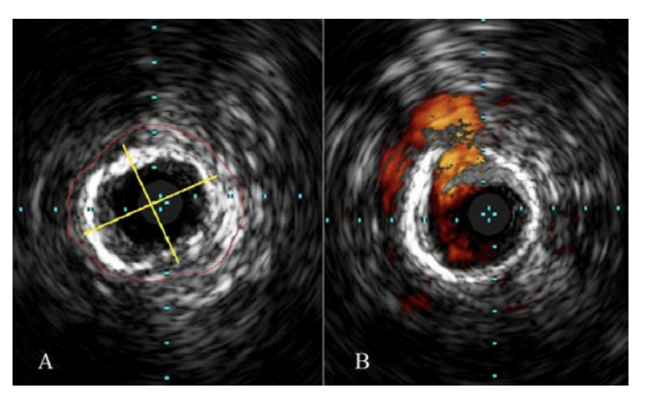

After achieving contralateral access, antegrade crossing of the left AT could not be achieved. Pedal access was then obtained via micropuncture technique with a 4 Fr sheath (Cook), and intraluminal crossing was accomplished under ultrasound guidance. IVUS was then performed via the retrograde approach. Using IVUS, the distance from the internal elastic lamina (IEL) to IEL was measured, and the vessel diameter was quantitated at 4.0 mm. Extensive 360° medial calcinosis and fibrosis in the AT were appreciated (Figure 2A).

Dilatation of the diseased segment of the left AT into the left popliteal was then done with an Armada 4.0 mm in diameter (Abbott) up to 16 atm. This high pressure was needed for full balloon expansion. Following percutaneous transluminal angioplasty (PTA), IVUS revealed a focal dissection in the AT fibrotic/calcified ring not identified on the angiogram. Based on the iDissection grading of dissections, this was classified as C2 (Figure 2B).6